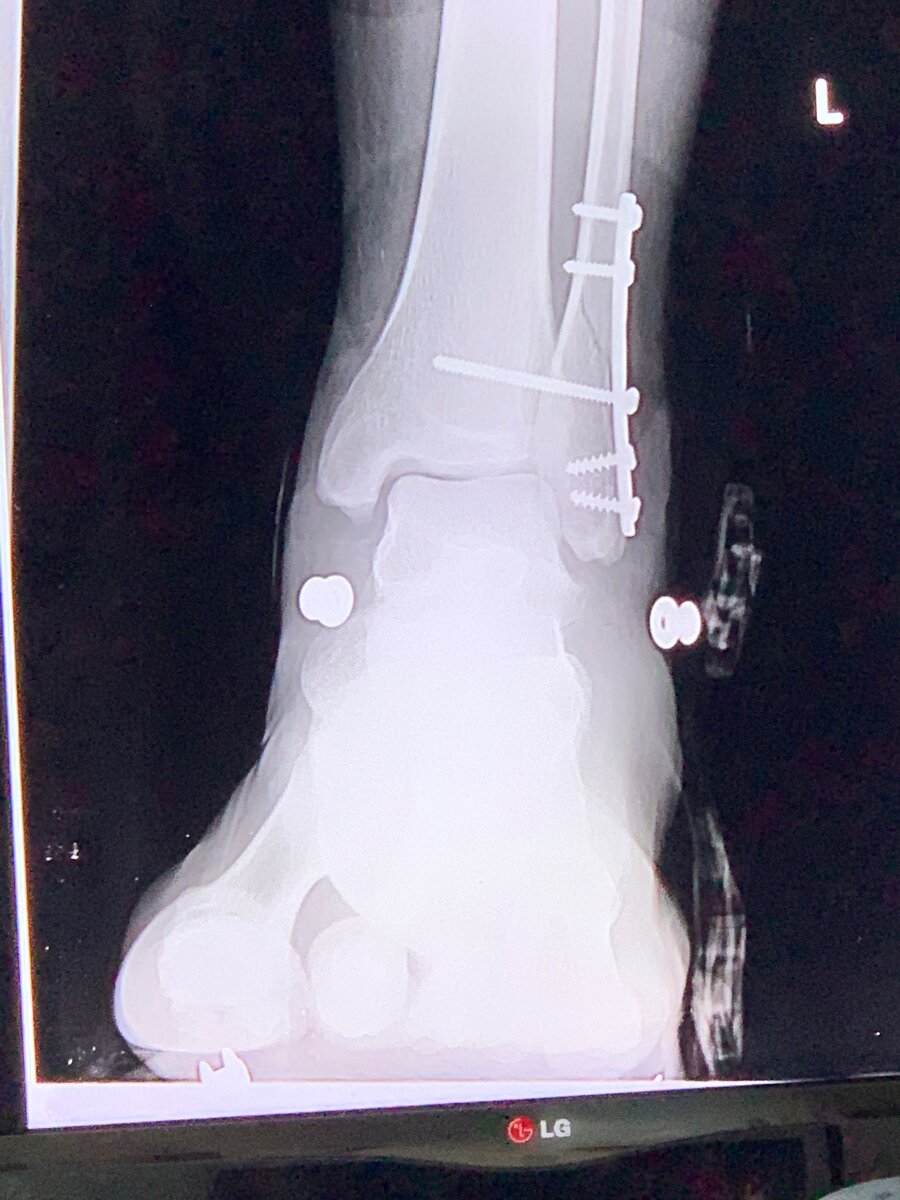

Перелом лодыжек – это внутрисуставное повреждение, поэтому помимо помощи травматолога, при внутрисуставных повреждениях всегда необходима работа с реабилитологом.  Перелом лодыжек – это внутрисуставное повреждение, поэтому помимо помощи травматолога, при внутрисуставных повреждениях всегда необходима работа с реабилитологом.